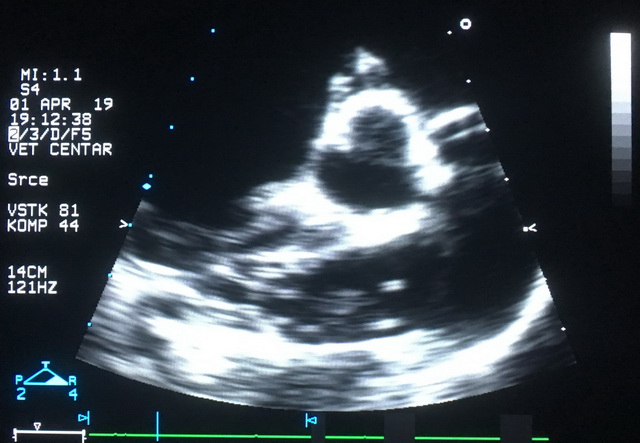

Nakon utvrđene dijagnoze, neophodno je sprovesti dodatna ispitivanja tako što se načini rendgenski snimak pluća i ultrazvučni pregled srca i glavnih plućnih arterija (slika 3 i 4). Ovi rezultati omogućavaju tačnu procenu ozbiljnosti infekcije i pravilan izbor daljeg načina nege i lečenja.

Povišenje plućnog pritiska, koje predhodi slabosti srca, može se na vreme uočiti kompetentnim ultrazvučnim pregledom. Zbog toga su neophodne kardiološke kontrole svih pacijenata inficiranih ovim parazitom, bez obzira na početni stadijum bolesti i bez obzira na primenjeni način lečenja (slika 6).